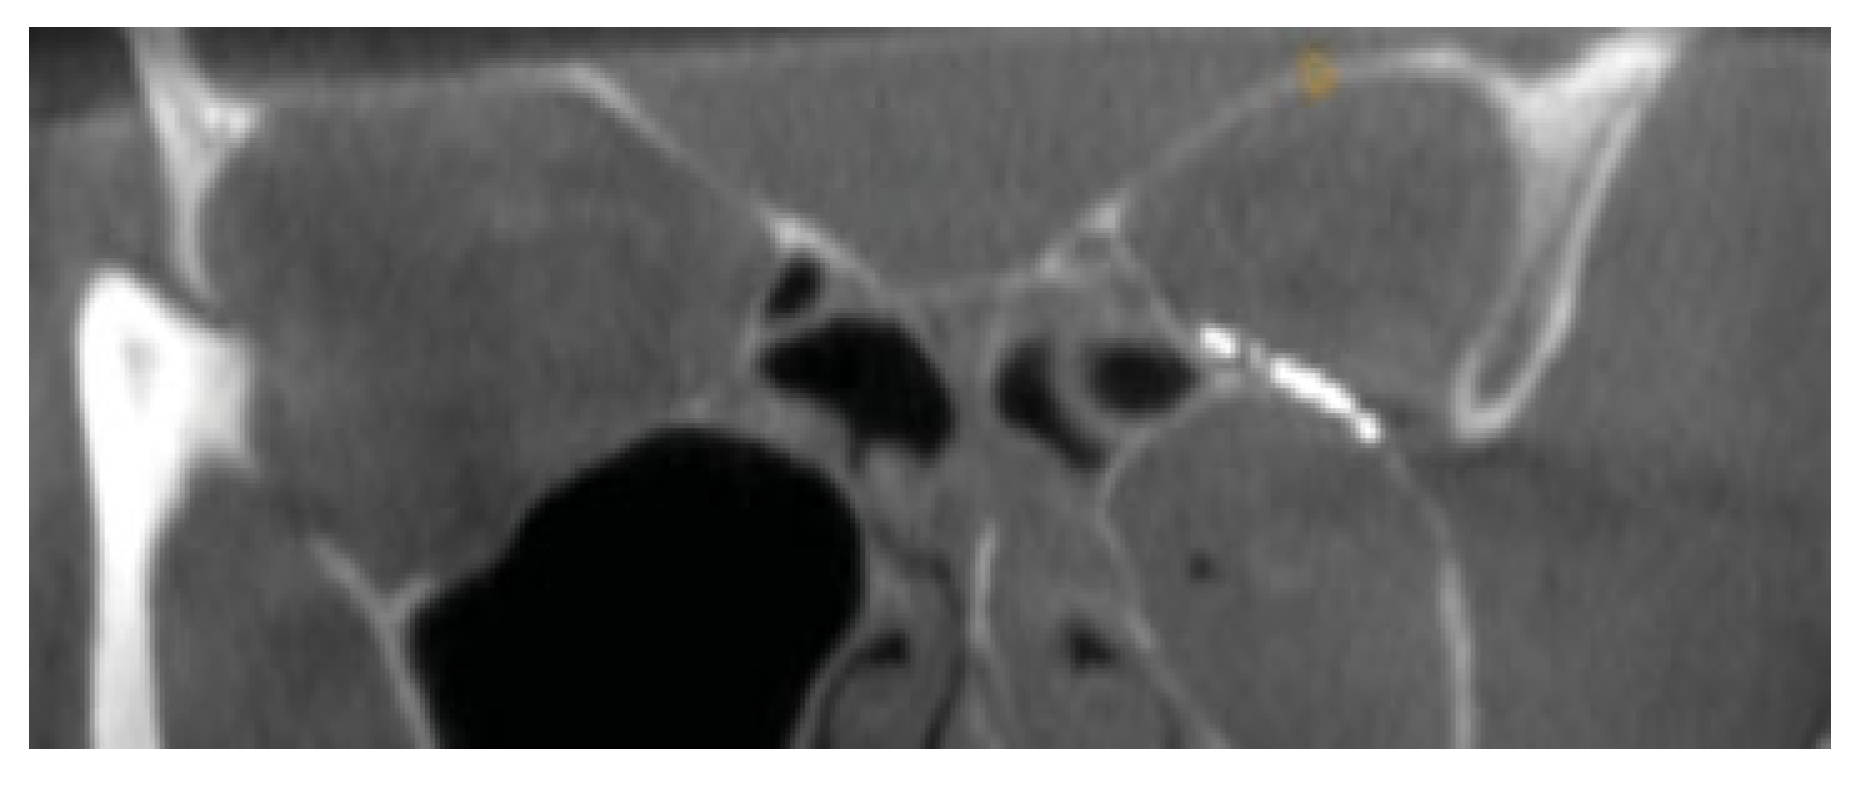

Figure 4.

Intra-operative coronal CT scan of posterior ledge and precise relationship to the titanium implant.

Figure 5.

Coronal view with correct adaptation of the plate at medial aspect of the inferior orbital fissure.

A 59-year-old female presented to the maxillofacial outpatient department following a mechanical fall resulting in a left orbital floor fracture. Enophthalmos of 2 mm was present and a CT scan revealed a large floor defect (Figure 2 and Figure 3). Diplopia was present on upward gaze. A rapid prototyping model was fabricated and a Synthes titanium orbital plate was further adapted preoperatively. The orbital floor was accessed via a mid-lid approach and the modified titanium orbital plate was inserted. No further adaptation of the plate was required and the time taken from insertion of the plate to final fixation was less than 1 minute, as no further adaptation was necessary. Position was confirmed with an intraoperative CT scan (O-arm, Medtronic [Medtronic, Minneapolis, MN]) (Figure 4, Figure 5 and Figure 6). The patient’s diplopia and enophthalmos had resolved 2 weeks postoperatively and no complications were noted at the 6th week follow-up.